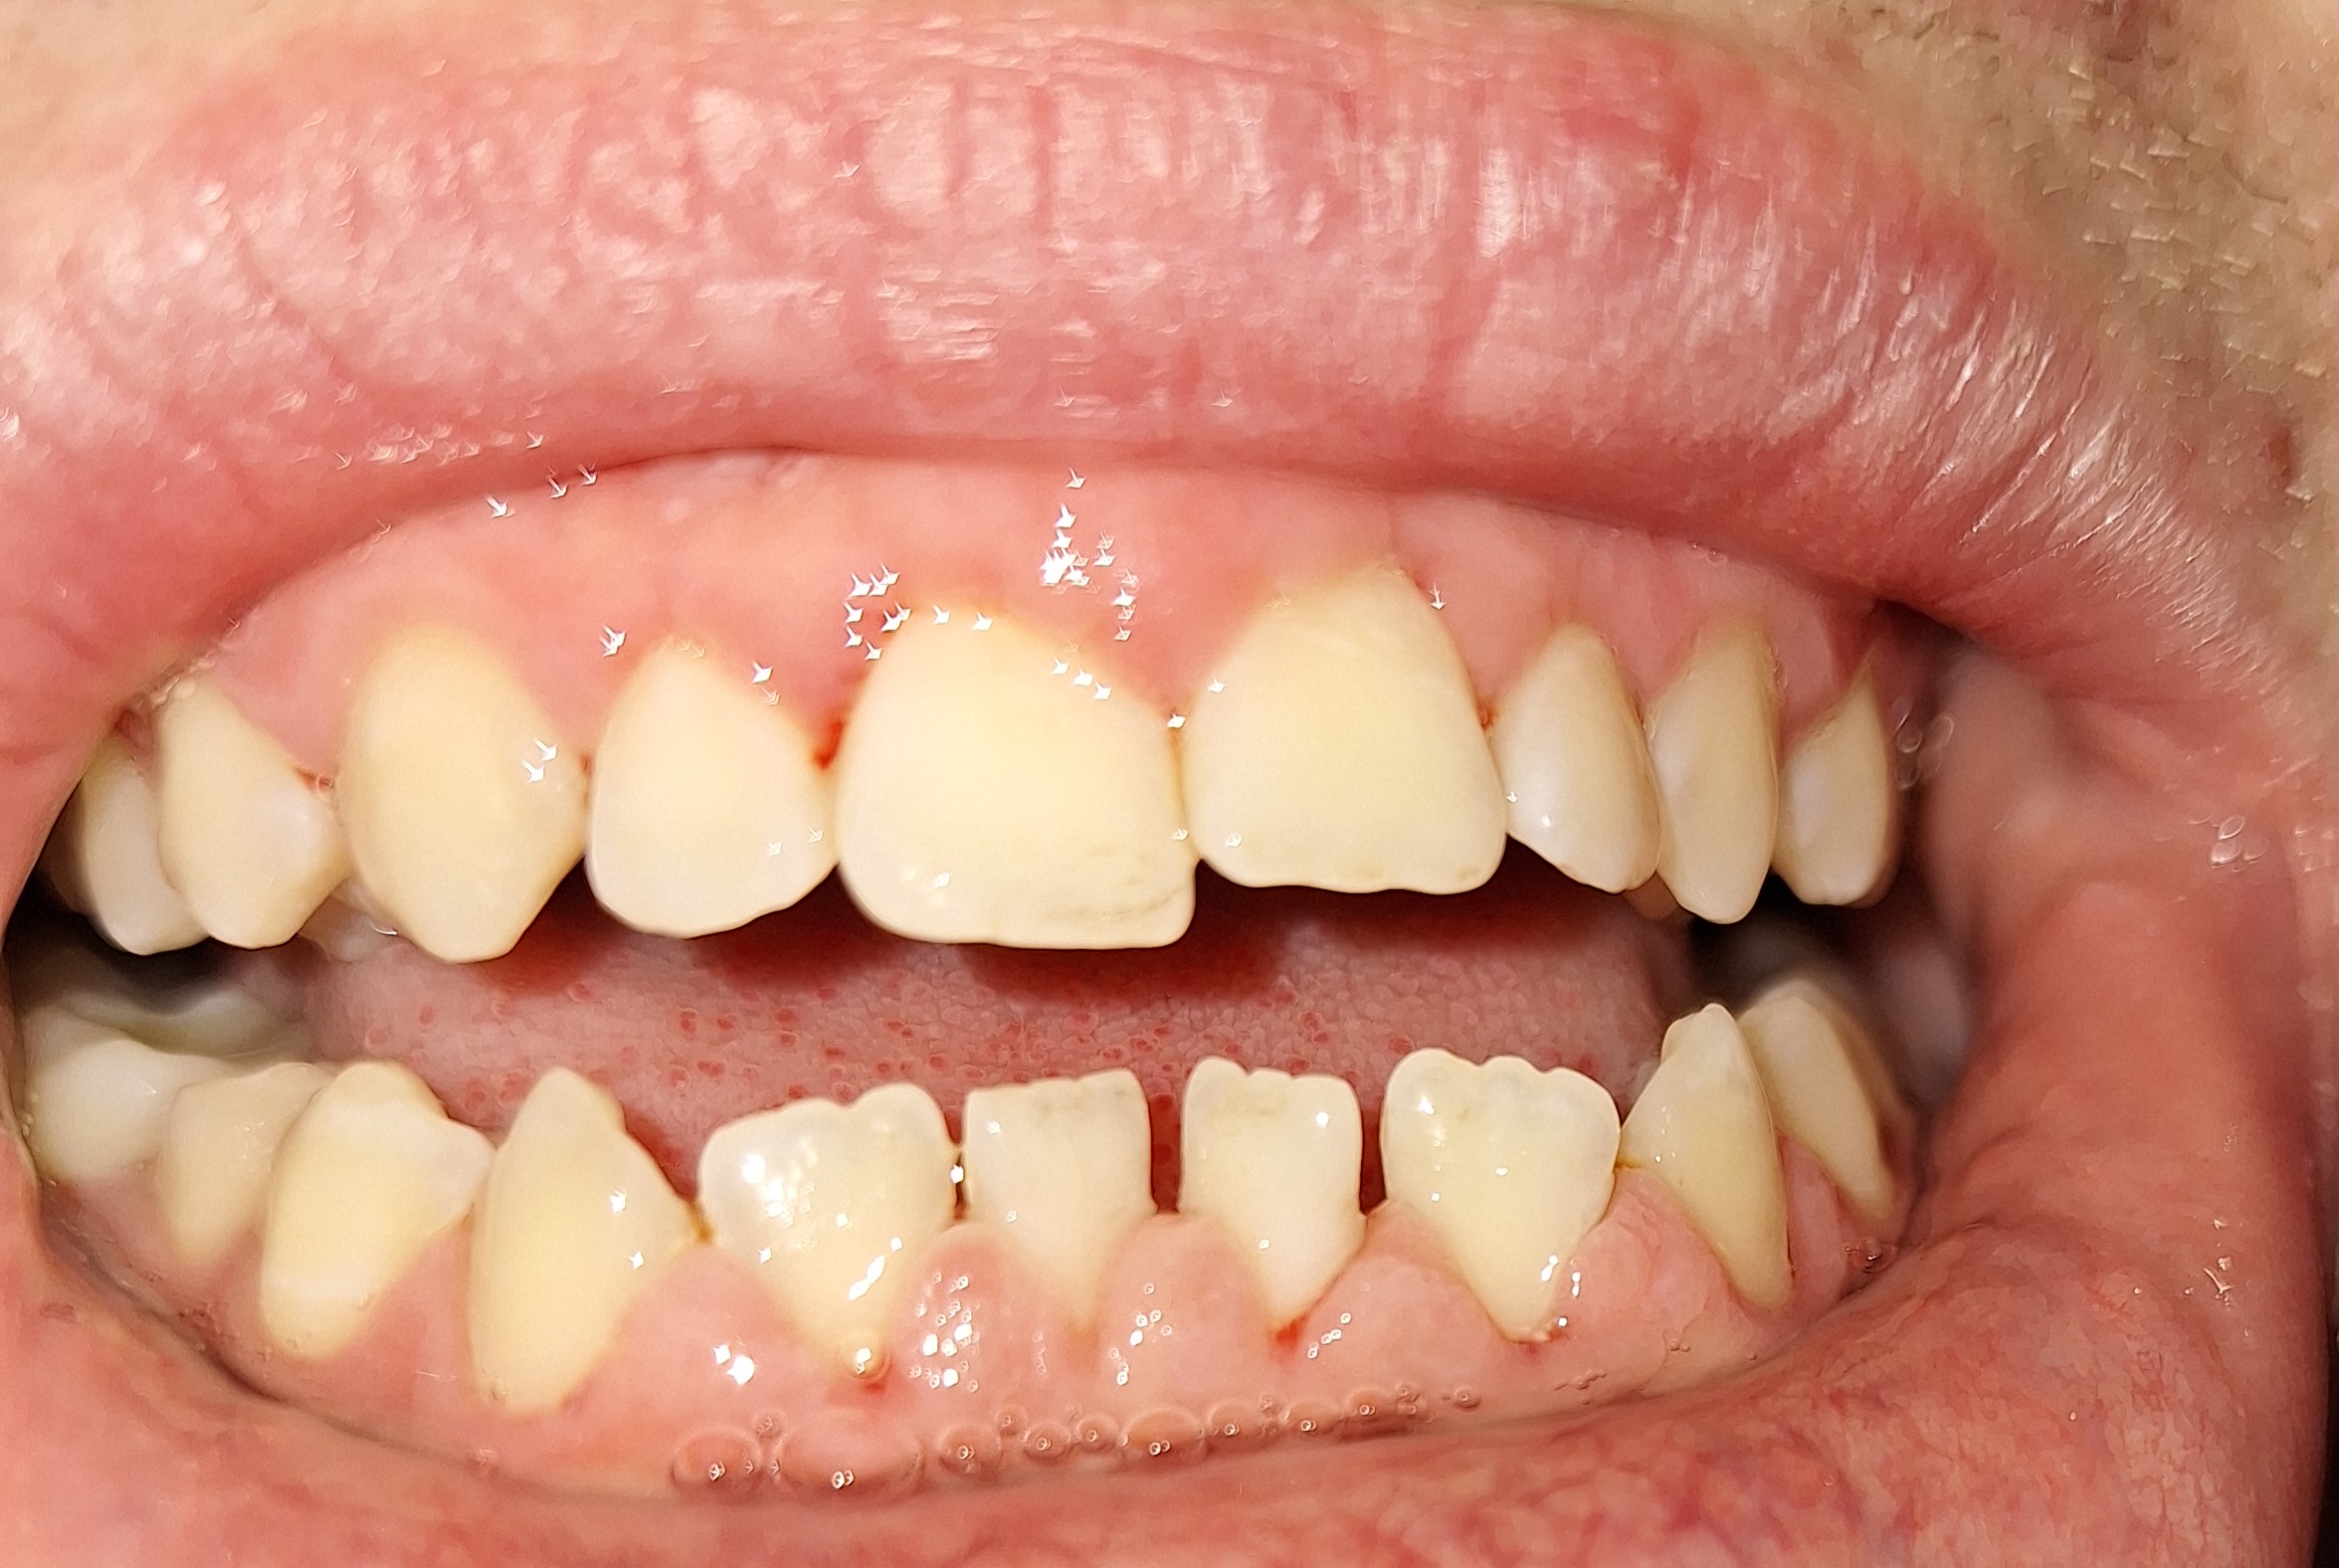

Сап медач.

Опустились дёсны в нескольких местах, обнажились шейки зубов. Чувствительные, болят от прикосновений, могут реагировать на холодное, горячее, сладкое.

Ситуация как примерно на пик2.

Предлагали два варианта:

1) Пластика десны, когда кусок кожи с нёба отрезают и пришивают к десне, чтобы закрыть оголившийся участок

2) Простое заделывание чувствительных мест пломбой/аналогом пломбы без пластики дёсен.

В первом случае меня беспокоит, что будет, если на оголившемся участке зуба есть кариес (сейчас из-за общей более тёмной природной пигментации шеек зубов + налёта не понятно), и я зашью этот кариес под кожу? Кариес будет прогрессировать под десной?

А во втором случае, дохтур сказал, что к заделанным пломбой шейкам зубов десна уже назад не прирастёт, даже если пересадить, то есть пластика дёсен будет невозможна.

ЧТО ДЕЛАТЬ, КАК ЛУЧШЕ ПОСТУПИТЬ?